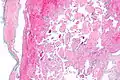

Intravascular papillary endothelial hyperplasia is a rare, benign tumor. It may mimic an angiosarcoma, with lesions that are red or purplish 5-mm to 5-cm papules and deep nodules on the head, neck, or upper extremities.[1][2]: 592

Pathology

Histopathology Images